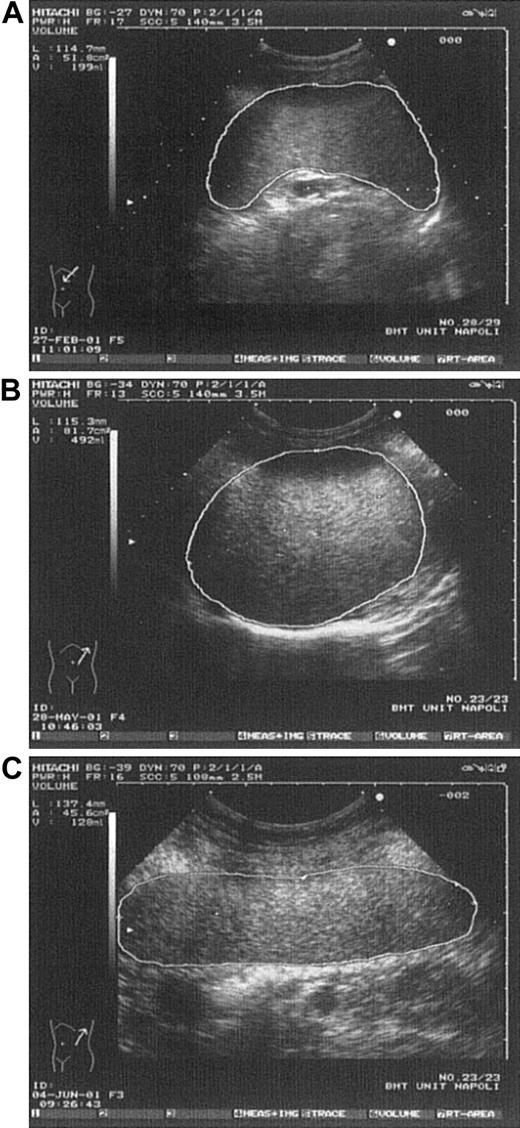

Various spleen shapes detected by US.

(A) Spleen in a control subject having normal longitudinal diameter and volume. (B) Spleen in a thrombocythemic patient having longitudinal diameter like that in Figure 2A but clearly enlarged volume. (C) Spleen in a control subject showing enlarged longitudinal diameter but normal volume (rodlike spleen).

In conclusion, in contrast to other studies employing different methods,5-7 we found a high rate of splenomegaly in patients with ET by using US measurements of volume (Figure1). These findings are consistent with those of another series, in which spleen volume was measured by a radionuclide technique (single-photon emission CT).4Because the spleen is an irregularly shaped organ that may enlarge at different rates in its various dimensions, physical examination1-3 and imaging using one-dimensional measurements5-7 may underestimate the true organ size, thus suggesting an erroneously low incidence of splenomegaly in patients with ET. Multidimensional US spleen-volume measurement (defined as the integration of longitudinal diameter, perimeter, and area) is a rapid, reliable, and low-cost method for detecting the true spleen size (Figure 2). In addition, our data support the concept of clinical heterogeneity in patients with ET3,14 15; a role for spleen-volume measurement in subgrouping these patients will be better evaluated by studies in progress.